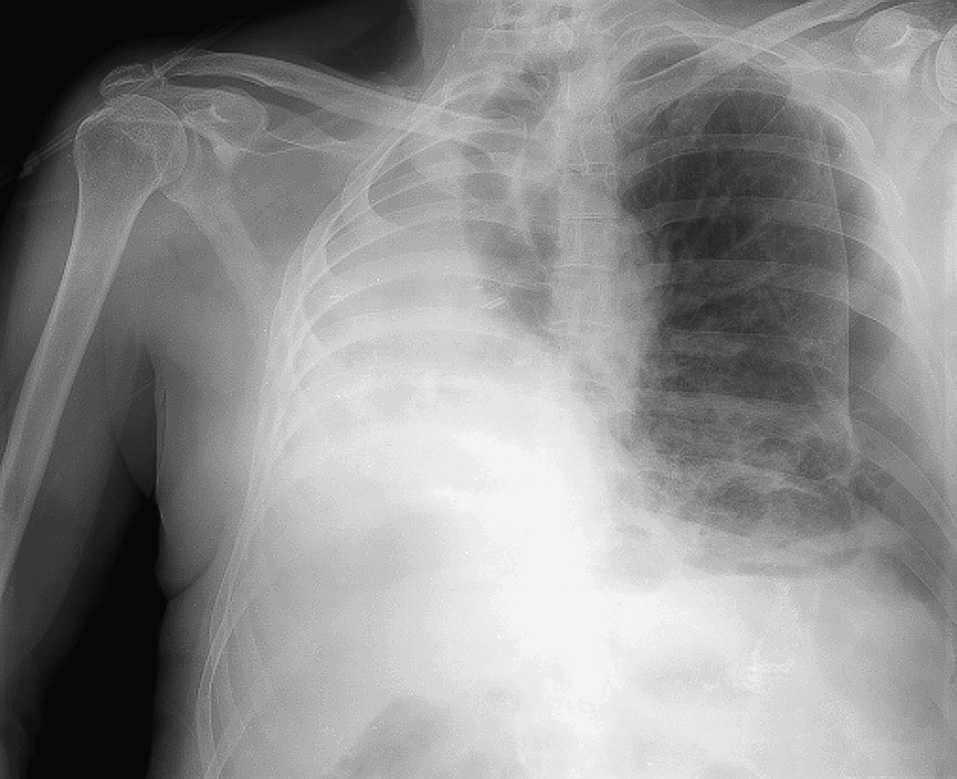

Presentamos el caso de un paciente con un neumotórax contralateral 2 años después de haber sido neumonectomizado por un carcinoma broncogénico. Debutó como disnea de 10 dÃas de evolución y no asoció insuficiencia respiratoria. Para su tratamiento fue suficiente la colocación de un drenaje endotorácico (fig. 1).

Fig. 1. Neumotórax izquierdo en paciente neumonectizado. El desplazamiento mediastÃnico es consecuencia de la neumonectomÃa.